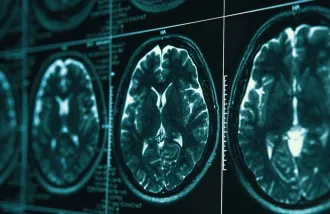

Neurons are built to last, but with age, bad things can happen to them. Wu Tsai Neuro affiliate Katrin Andreasson's work shows a lot of it is triggered by what’s happening to immune cells outside of the brain.